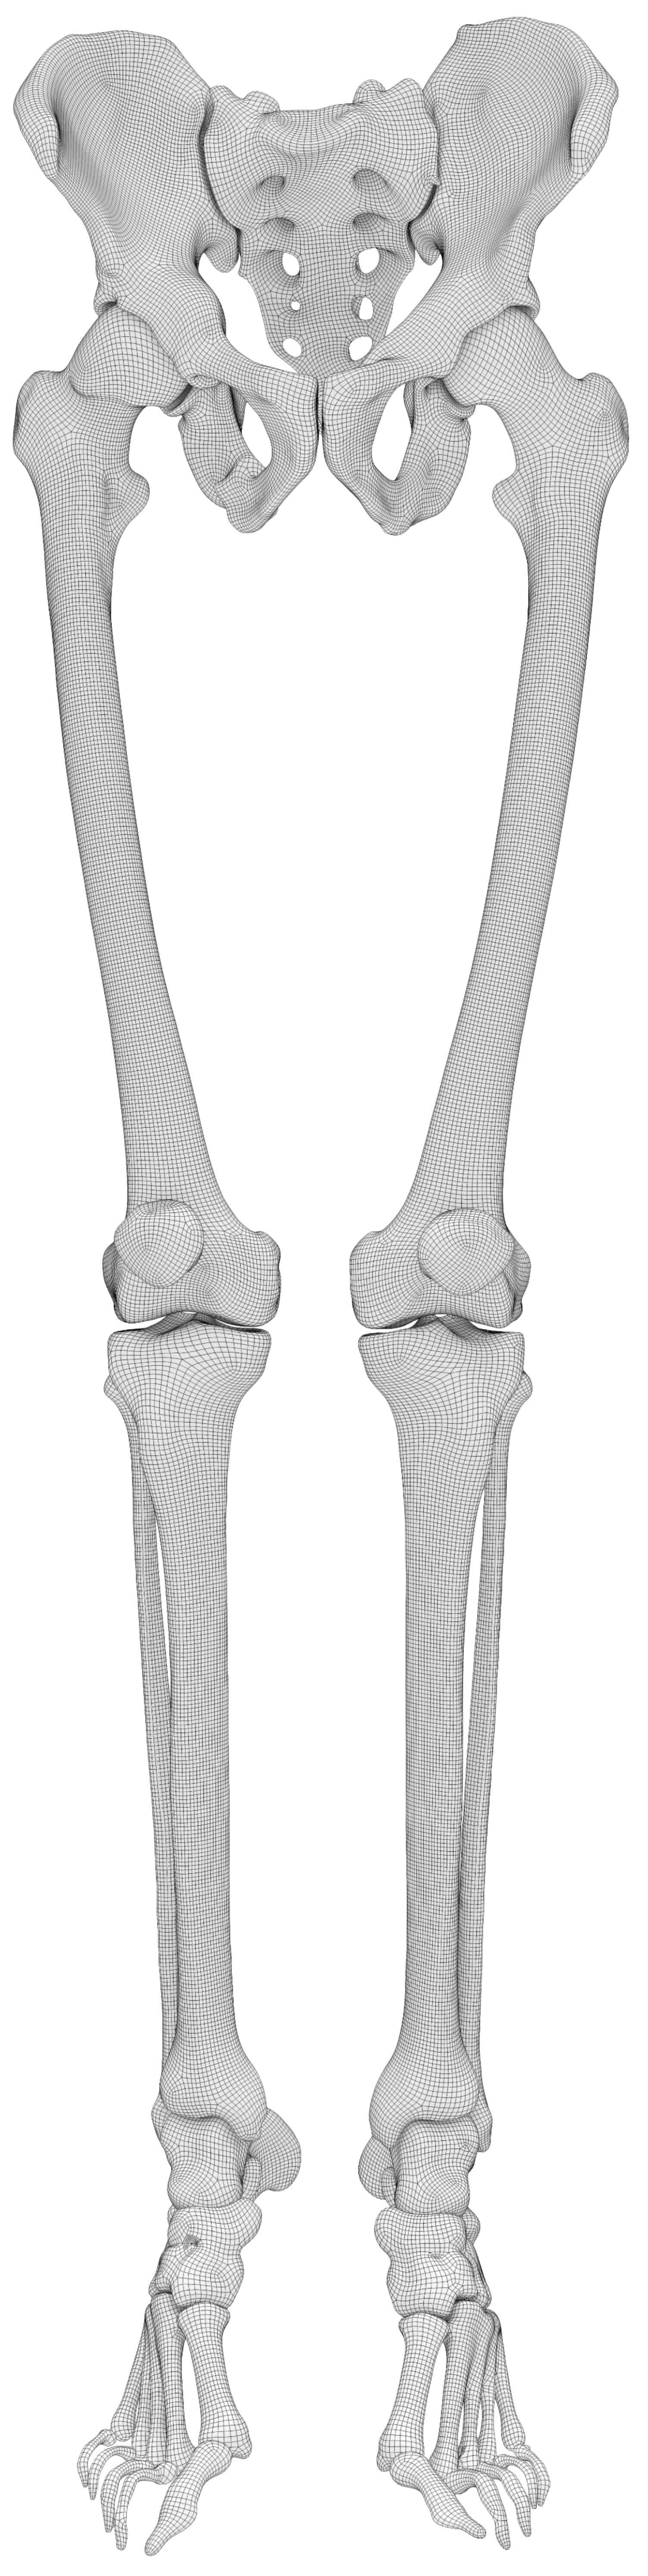

Welcome to

BoneHub

A Hub for Providing Large-Scale Population-Based 3D Bone Shapes

BoneHub Dataset

A comprehensive, harmonized dataset for 3D bone shapes, medical images, and related metadata.